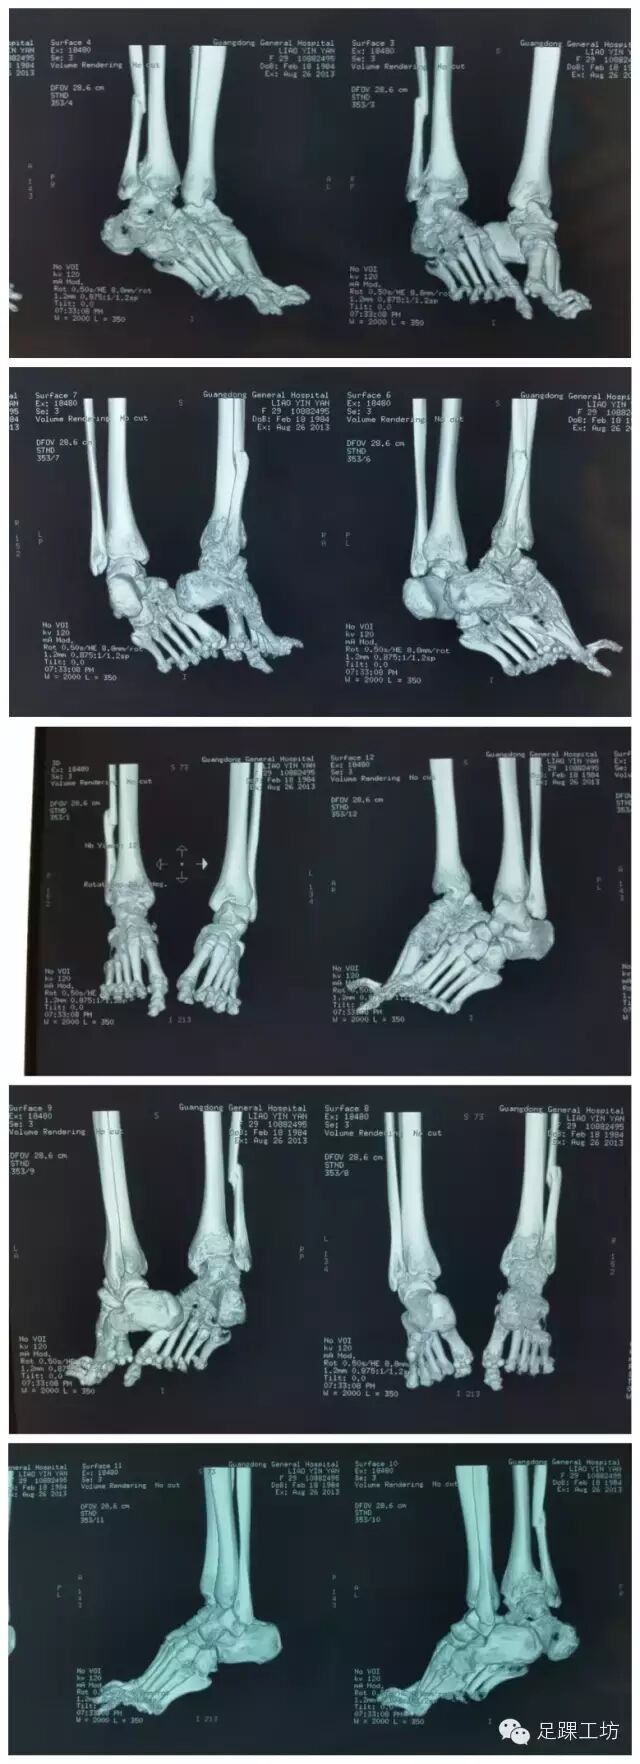

CT重建

该院行右踝部陈旧骨折、脱位手术治疗,术后患者右踝部仍有疼痛、活动受限。